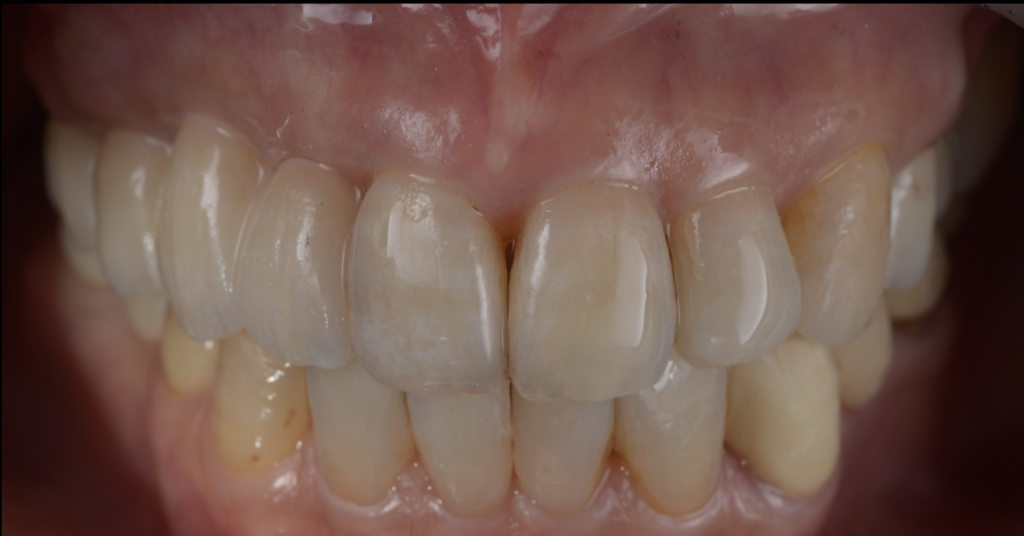

- 上下ともにインプラントブリッジで噛める機能を回復

- 奥歯が噛めないことで生じた切端咬合を、部分矯正で改善

- 少ない本数でも成立するように、噛み合わせと設計を最優先で再構成

- ブリッジは高強度ジルコニアを選択し、審美性よりも厚みと強度を確保

治療の工夫③:高強度ジルコニアを選び、審美より“強度と厚み”を優先

今回は、患者様が「噛めるようになりたい」という機能回復を最重視していたこと、

またブリッジ設計であることから、強度の高いジルコニアを選択しました。

高強度ジルコニアは、立体感や審美性(透明感)の表現がやや制限される一方で、

- 強度を確保しやすい

- ブリッジでの破折リスクを下げやすい

- 厚みを取って設計できるというメリットがあります。

今回は、理想的な審美表現よりも、厚みを確保して長期安定に寄せる設計にしています。